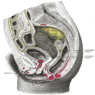

Prior to learning the microarchitecture of the Female Reproductive Tract, use the table below to review some of the gross anatomy of these tissues:

Structure Image

Cross Section of the Ovary OvaryXSection.gif

Arrangement of the Uterus, Ovary, and Uterine Tubes UterusOvaryTubes.gif

Gross Anatomical Location of the Uterus in the Pelvic Cavity UterusInPelvicCav.gif

Arrangement of the Uterus, Cervix, and Vagina UterusCervixVagina.gif

The Mammary Gland Mammary.gif